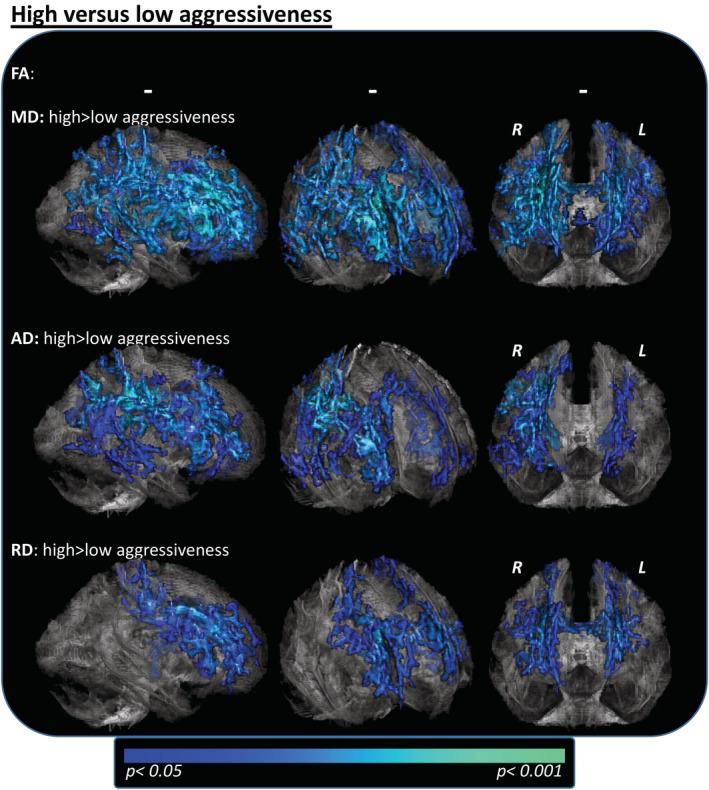

Numerous neuroimaging studies in amyotrophic lateral sclerosis (ALS) have reported links between structural changes and clinical data; however phenotypic and disease course heterogeneity have occluded robust associations. The present study used the novel D50 model, which distinguishes between disease accumulation and aggressiveness, to probe correlations with measures of diffusion tensor imaging (DTI). DTI scans of 145 ALS patients and 69 controls were analyzed using tract-based-spatial-statistics of fractional anisotropy (FA), mean- (MD), radial (RD), and axial diffusivity (AD) maps. Intergroup contrasts were calculated between patients and controls, and between ALS subgroups: based on (a) the individual disease covered (Phase I vs. II) or b) patients' disease aggressiveness (D50 value). Regression analyses were used to probe correlations with model-derived parameters. Case-control comparisons revealed widespread ALS-related white matter pathology with decreased FA and increased MD/RD. These affected pathways showed also correlations with the accumulated disease for increased MD/RD, driven by the subgroup of Phase I patients. No significant differences were noted between patients in Phase I and II for any of the contrasts. Patients with high disease aggressiveness (D50 < 30 months) displayed increased AD/MD in bifrontal and biparietal pathways, which was corroborated by significant voxel-wise regressions with D50. Application of the D50 model revealed associations between DTI measures and ALS pathology in Phase I, representing individual disease accumulation early in disease. Patients' overall disease aggressiveness correlated robustly with the extent of DTI changes. We recommend the D50 model for studies developing/validating neuroimaging or other biomarkers for ALS.

许多肌萎缩侧索硬化症(ALS)的神经影像学研究报告了结构变化与临床数据之间的联系;然而,表型和疾病过程的异质性阻碍了稳健的关联。本研究使用了新的 D50 模型,该模型区分了疾病积累和侵袭性,以探究与扩散张量成像(DTI)测量的相关性。使用基于分数各向异性(FA)、平均(MD)、径向(RD)和轴向扩散系数(AD)图的基于束的空间统计分析,对 145 名 ALS 患者和 69 名对照者的 DTI 扫描进行了分析。在患者和对照组之间、在基于个体疾病覆盖(I 期与 II 期)的 ALS 亚组之间以及在基于患者疾病侵袭性(D50 值)的 ALS 亚组之间计算了组间对比。回归分析用于探究与模型衍生参数的相关性。病例对照比较显示,广泛的 ALS 相关白质病变伴有 FA 降低和 MD/RD 增加。这些受影响的通路也与累积疾病相关,MD/RD 增加,这主要是由 I 期患者亚组驱动的。对于任何对比,I 期和 II 期患者之间均未观察到显著差异。疾病侵袭性高(D50 < 30 个月)的患者在前额和顶叶双通路中显示出 AD/MD 增加,这与 D50 的显著体素回归一致。D50 模型的应用揭示了 DTI 测量与 I 期 ALS 病理学之间的关联,代表了疾病早期的个体疾病积累。患者的整体疾病侵袭性与 DTI 变化的程度密切相关。我们建议使用 D50 模型进行开发/验证 ALS 的神经影像学或其他生物标志物的研究。